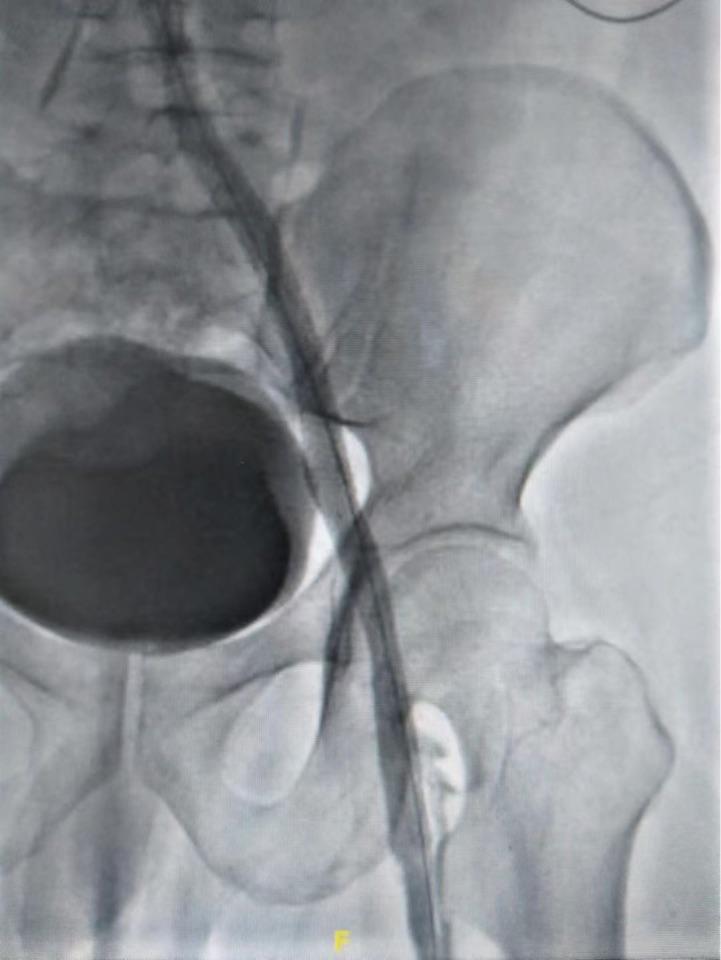

天无绝人之路,缝隙中通过病变